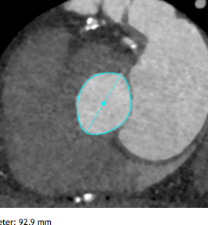

主动脉瓣环周长:97.8mm(瓣上3mm结构周长89mm);

左室流出道周长:92.9mm;